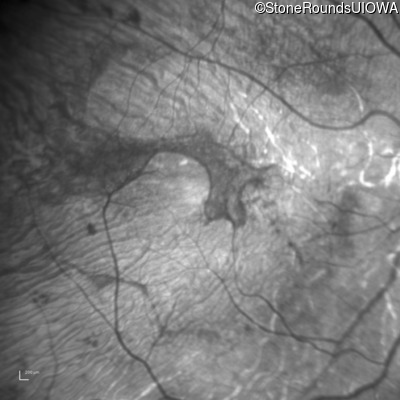

Infrared Fundus Photograph - Left - 20/63

Exemplar